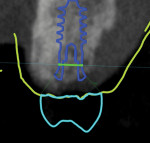

A digital volume or cone-beam computed tomography was acquired (digital imaging and communications in medicine [DICOM]) along with intraoral scans of the patient's remaining dentition (STL files) and virtual interocclusal records (Virtuo Vivo™, Straumann, straumann.com). The DICOM and STL files were imported into planning software (coDiagnostiX®, Straumann), and the datasets were registered and merged. A virtual diagnostic design was developed using CARES® Visual software (Straumann). Using Synergy™ interface, the treatment team was able to determine the appropriate 3-dimensional (3D) restoration-driven implant position (Figure 5 and Figure 6).

The planned implant position was confirmed and accepted by the treatment team. A surgical template was designed using coDiagnostiX software (Figure 7). This template was to be used as a static guide (s-CAITS) to facilitate restoration-driven 3D positioning of the chosen implant (Straumann® TLX RT Ø 4.5 mm x 8 mm, Straumann). The surgical template design incorporated a channel to facilitate irrigation during implant placement. Once the template design was approved, it was exported for manufacture using a digital workflow.